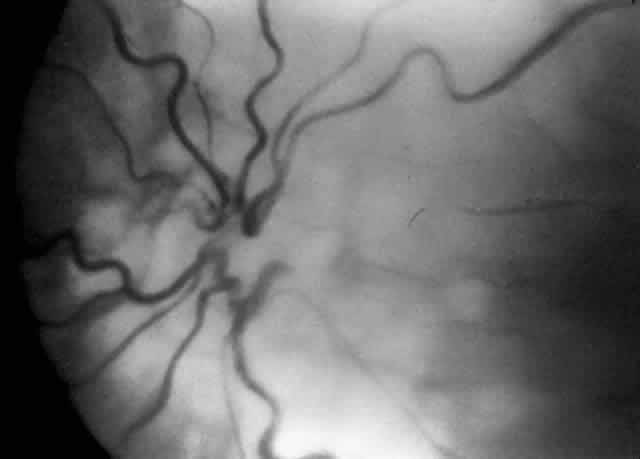

COATS' DISEASE Coats' disease is an example of a vitreoretinal congenital vascular disease in which vitreous traction often plays a role leading to both preretinal and subretinal hemorrhage with resultant retinal detachment. Children with Coats' disease have been managed with vitreous surgery, scleral buckling, trans-scleral diathermy, cryotherapy, laser therapy alone, and laser therapy accompanied by injectable dyes (Fig. 7).40–42 Many different techniques have been employed because frequently neither the vessel abnormalities nor the vitreous traction can be resolved completely. With the possible advent of enzymatic surgery, such as use of plasmin or chondroitinase, it is hoped that a cleaner and more complete reduction of vitreoretinal traction will help advance the involution of these abnormal vessels without concurrent vitreous or subretinal hemorrhage.43